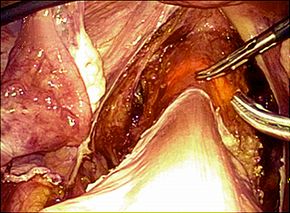

腹腔鏡下胆嚢摘出術の実際

全身麻酔をかけた状態で手術を行います。腹腔鏡下手術では腹部に4カ所の穴、単孔式

腹腔鏡下手術では1カ所の穴を開け、炭酸ガスをおなかの中に入れ、その穴から内視鏡

や手術鉗子を挿入し、画面を見ながら胆嚢を摘出する方法です。

単孔式腹腔鏡下胆嚢摘出術

腹腔鏡手術で胆嚢の摘出と総胆管結石の摘除を同時に行います。胆嚢摘出後、十二指腸

上部総胆管を切開し、胆道鏡を用いて直視下に胆石を除去します。

採石後は胆道鏡で結石遺残のないことを確認します。その後胆管切開部を腹腔鏡下に

体内で結紮縫合を行い、閉鎖します。